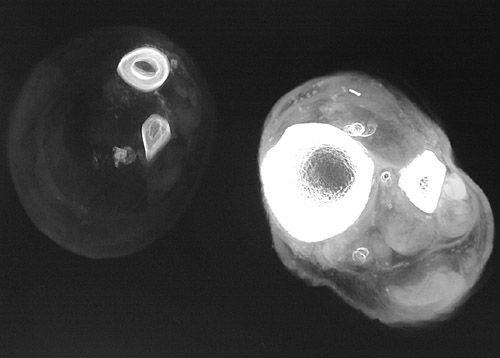

The amount of x-ray exposure can be varied. In general, to reduce radiation exposure to the patient, the lowest dose of x-radiation possible is used. The amount of x-ray exposure is a function of time and intensity, both of which can be varied. A longer time of exposure or a more intensive beam of x-rays will result in more radiolucency. Films exposed in this fashion are "overexposed" or "overpenetrated." Conversely, film exposed for a shorter time or with a less intense beam will appear "underexposed" or "underpenetrated." The image below compares two different degrees of penetration of the lower leg in cross section with tibia and fibula.